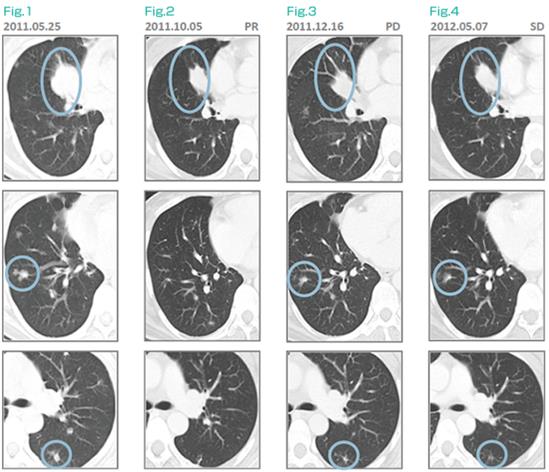

39岁女性,无吸烟史,2011年4月诊断EGFR阳性肺癌,胸椎转移,cT4N0M1b。6月开始口服厄洛替尼(特罗凯),10月CT检查略有缓解,但已发生病理性骨折,无法站立。11月开始在濑田接受αβT细胞(制备过程中洗除部分Treg)+厄洛替尼治疗,12月CT发现肿瘤进展,诊断厄洛替尼耐药。此时按照标准疗法应该停止厄洛替尼,改为化疗,但患者不同意。制剂继续接受厄洛替尼+细胞治疗,在2012年1月、2月、5月、6月的CT评估中,肿瘤保持稳定(SD)。